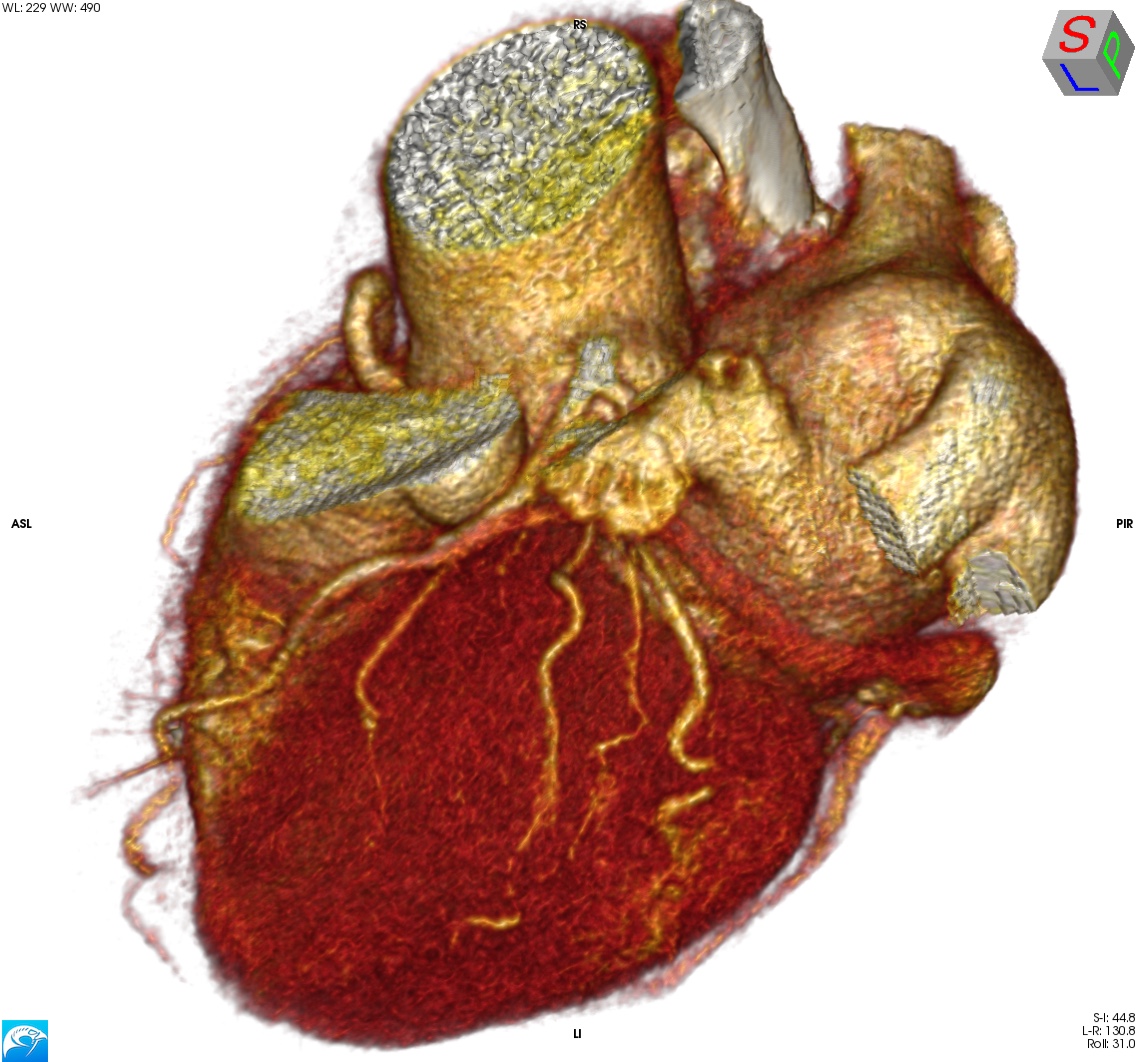

Όταν, λοιπόν, αποφασίζουμε να προχωρήσουμε, το αποτέλεσμα πρέπει να είναι κάπως έτσι:

Και στις MPR τομές, να μη φαίνεται σκιαγράφηση του σώματος του ωτίου — ακόμα και ένα μικρό peri-device leak (PDL) θα τo «ασπρίσει» –, ούτε βέβαια θρόμβος (device-related thrombosis, DRT).

Για σύγκριση, οι εικόνες CTA\ECG πριν την τοποθέτηση της συσκευής: